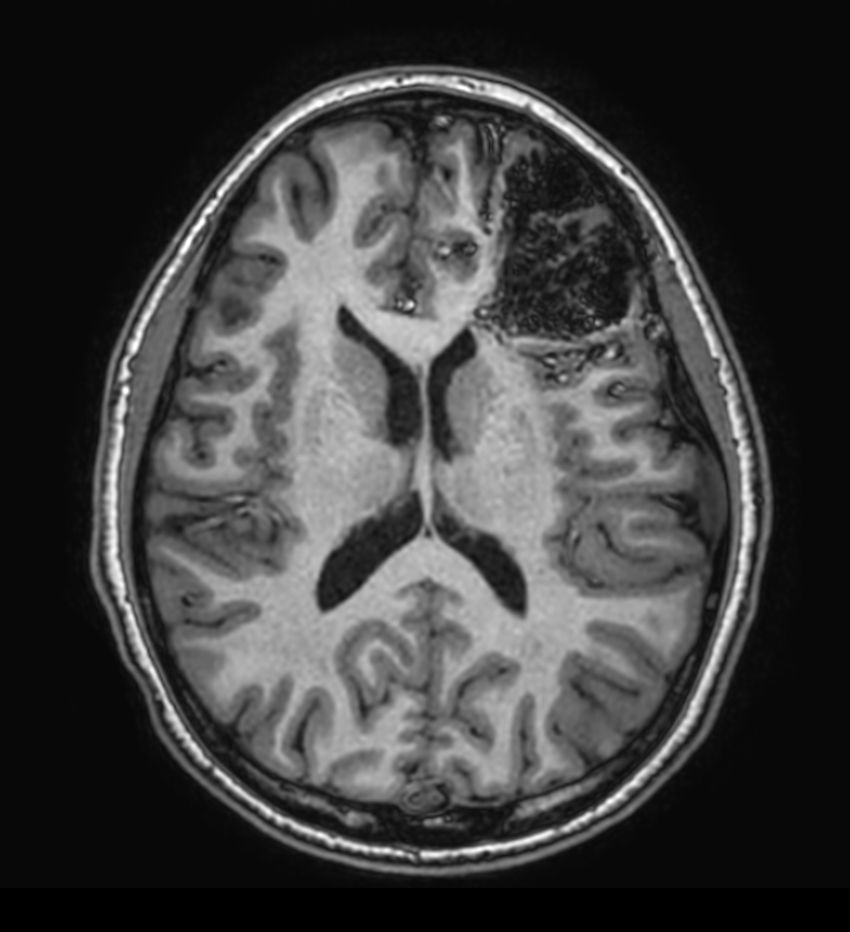

Pediatric brain with AVM

Pediatric patient with frontal brain AVM. MultiVane XD is used to achieve high resolution diagnostic images, even in the case of severe patient motion. SWIp sequence is added to acquire exquisite susceptibility contrast. The 3D sequences with isotropic voxel size enable reformats in any plane without loss of resolution. And 4D-TRAK XD, a fast, dynamic contrast-enhanced MR Angiography method allows to achieve high spatial and temporal resolution simultaneously. Integration of Compressed SENSE acceleration technique enables speeding up of the entire exam.

3D T2w FLAIR - Axial reformatCompressed SENSE